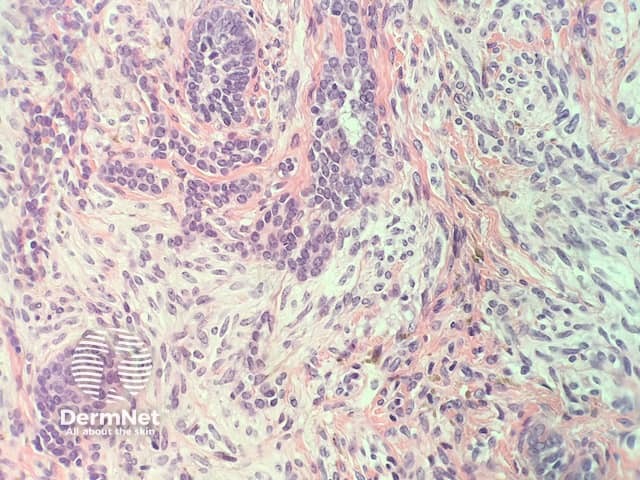

In combined trichoepithelioma and cellular blue naevus, the histopathology shows a fairly well-circumscribed biphasic dermal proliferation involving the full thickness of the dermis and shows tongues of rounded tumour fronts (figure 1). The tumour is composed of intimately mixed populations of melanocytes and basaloid cells. The basaloid cells anastomose in a lace-like pattern and form horn cysts focally (figure 2,3). The follicular component is surrounded by a prominent stroma, which is condensed around the basaloid islands as hair papilla-like structures. The melanocytic component consists of islands of plump spindled cells with abundant pale cytoplasm and minimal pigment and rarer slender dendritic melanocytes with heavy melanin pigmentation (figure 4).

Figure 2

Figure 3